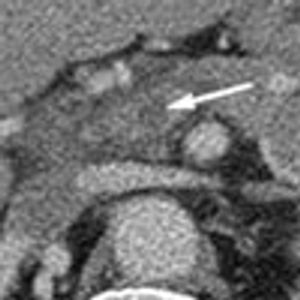

Acute abdominal pain, fever, and chills prompted a 51-year-old man to visit his local hospital twice in one week. On both visits, a clinical and laboratory workup was negative. He then presented to a tertiary care center with worsening symptoms. His history included hypertension and tobacco and alcohol use.